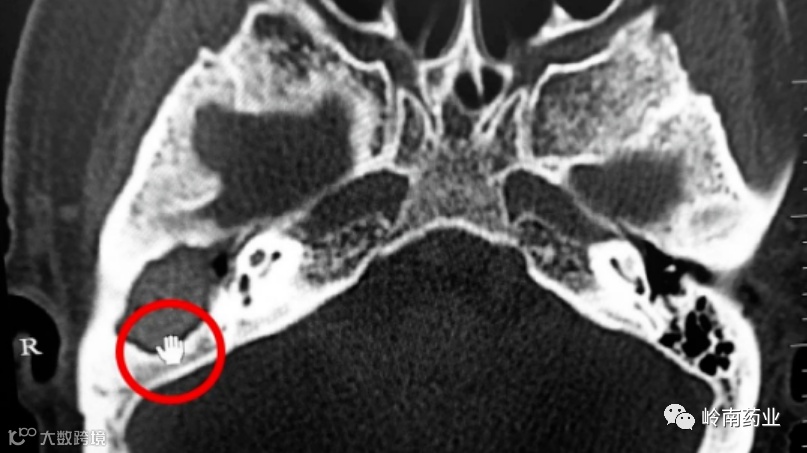

78岁大伯常掏耳朵

检查结果令他慌了

警惕!外耳道胆脂瘤

早期易误诊漏诊